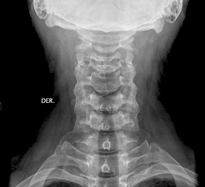

Columna Cervical AP: Con el paciente de pie o en decúbito, el haz de rayos se dirige a la altura de C4 (manzana de Adan), angulado 15 o a 20 o hacia cefálico